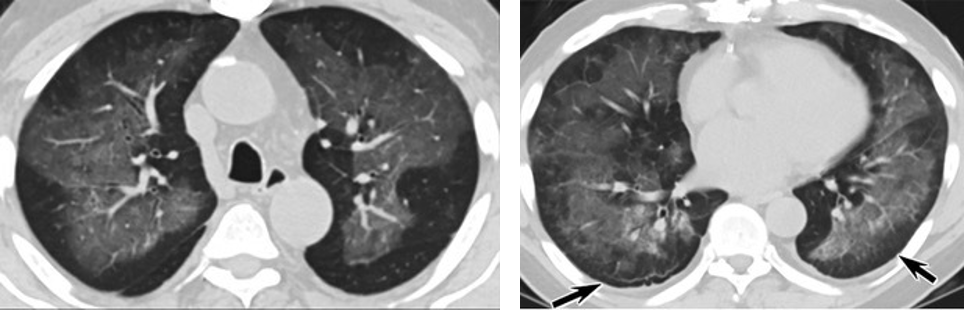

6天后的轴向CT平扫图像显示毛玻璃影变为实变和轻度结构扭曲。(同一病人CT影像)

同一病人CT影像显示,中、下肺轴位CT平扫显示毛玻璃样混浊伴胸膜下保留(箭头)疑点二,中国科研工作者从60篇研究论文中筛选出142位电子烟肺炎患者的250张影像图片,邀请3位放射科权威专家,对上述全部影像图片、相关病人临床信息以及文献原文进行了仔细全面研究与审查,发现:16位被文献报道为电子烟肺炎的患者被专家判定为“病毒性感染”,即有可能是新冠肺炎的“疑诊患者”,其中更有5位临床症状和治疗情况相对完整的患者被判定为“中度可疑”。